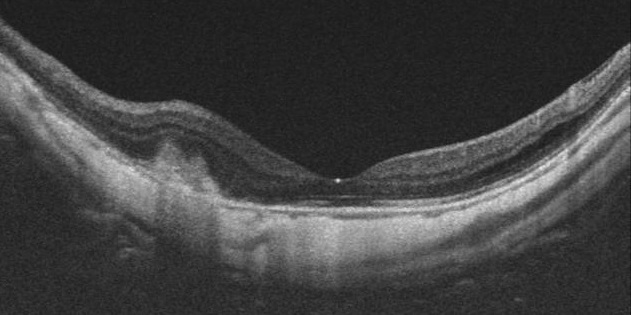

・診断: 加齢黄斑変性に類似していますが、強度近視による眼底の特徴や光干渉断層計(OCT)画像における特徴を慎重に見極めることで診断可能です。黄斑部の眼底に出血があっても脈絡膜新生血管がない場合(単純出血)もあり得ますので、光干渉断層血管撮影(OCTA)で脈絡膜新生血管の有無を調べます。

※上記症例に抗VEGF薬注射を行って2カ月目の眼底写真とOCT画像。